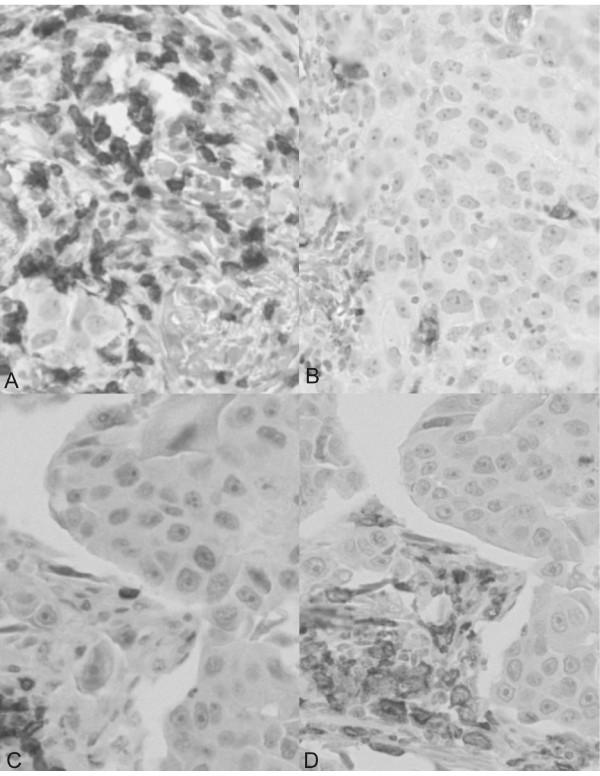

METHODS

A tissue microarray (TMA) including 894 ductal and 164 lobular breast cancers was stained with antibodies recognizing CD4, FOXP3, and IL-17 by standard immunohistochemical techniques. Lymphocyte counts were correlated with clinico-pathological parameters and survival.

CD4(+) lymphocytes were more prevalent than FOXP3(+) TILs whereas IL-17(+) TILs were rare. Increased numbers of total CD4(+) and FOXP3(+) TIL were observed in ductal, as compared with lobular carcinomas. High grade (G3) and estrogen receptor (ER) negative ductal carcinomas displayed significantly (p < 0.001) higher CD4(+) and FOXP3(+) lymphocyte infiltration while her2/neu over-expression in ductal carcinomas was significantly (p < 0.001) associated with higher FOXP3(+) TIL counts. In contrast, lymphocyte infiltration was not linked to any clinico-pathological parameters in lobular cancers. In univariate but not in multivariate analysis CD4(+) infiltration was associated with significantly shorter survival in patients bearing ductal, but not lobular cancers. However, a FOXP3(+)/CD4(+) ratio > 1 was associated with improved overall survival even in multivariate analysis (p = 0.033).